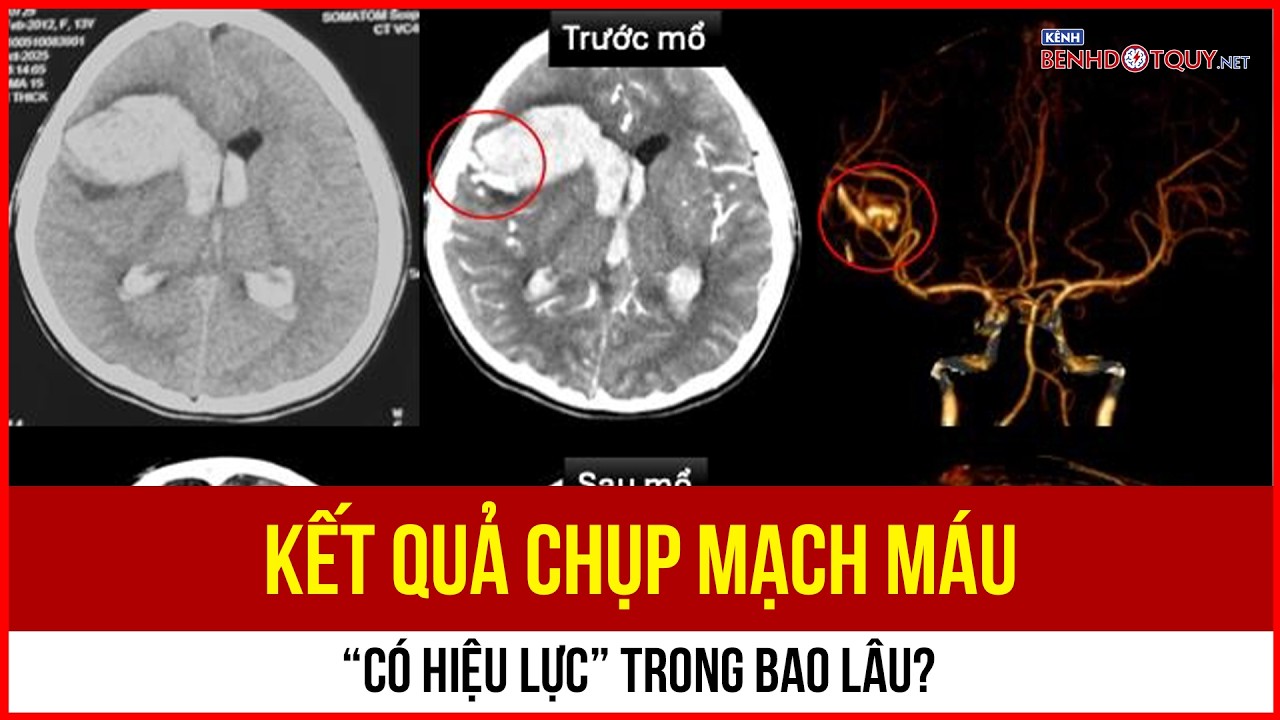

- Đột quỵ

Sau phẫu thuật, bệnh nhân có thể gặp biến chứng đột quỵ

Sau phẫu thuật, bệnh nhân có thể gặp biến chứng đột quỵ